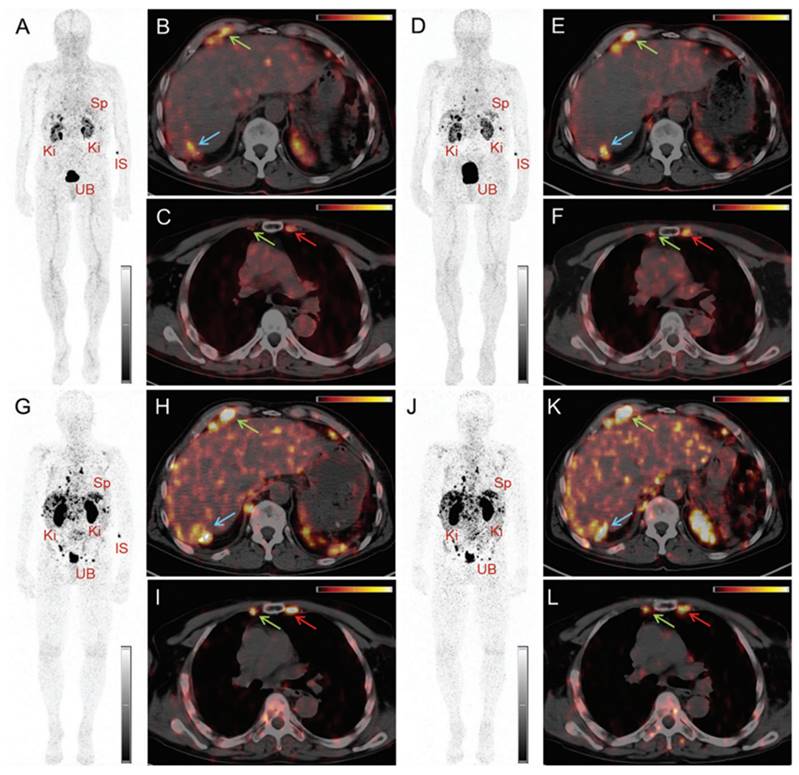

Moreover, the clinical feasibility of [152Tb]Tb-DOTATOC for PET/CT imaging was further investigated in a patient with a metastatic neuroendocrine neoplasm [88]. The study's findings showed the effectiveness of [152Tb]Tb-DOTATOC (145 MBq, 2.5 MBq/kg) in visualizing small metastases, though the image quality was found to be noisier compared to PET images obtained using [68Ga]Ga-DOTATOC (104 MBq) (Figure 10-11). Nonetheless, the PET/CT scan using [152Tb]Tb-DOTATOC effectively detected all the metastatic lesions that had previously been identified with [68Ga]Ga-DOTATOC, confirming its diagnostic potential [88]. Additionally, the clinical potential of terbium-152 was also evaluated using a PSMA-targeting agent, PSMA-617, which is currently used in combination with lutetium-177 ([177Lu]Lu-PSMA-617 (PluvictoTM)) for the treatment of metastasized castration-resistant prostate cancer (mCRPC) [77]. The study revealed that [152Tb]Tb-PSMA-617 and [177Lu]Lu-PSMA-617 exhibited similar pharmacokinetic profiles in tumor-bearing mice, which was consistent with previous in vitro findings [89]. Encouraged by these promising preclinical results, the researchers conducted the first-in-human application of [152Tb]Tb-PSMA-617 for PET/CT imaging in a patient with mCRPC (administered activity: 140 MBq). The imaging procedure was well-tolerated by the patient, and the obtained images facilitated the detection of all the metastatic lesions that were previously identified by [68Ga]Ga-PSMA-11 PET/CT scans [89]. While terbium-152 holds promise for PET/CT imaging in patients for pre-therapeutic dosimetry and treatment planning, the superior quality of images obtained with widely-available gallium-68 raises questions about the clinical applicability and usefulness of terbium-152.

Figure 10

PET/CT images of a patient with neuroendocrine neoplasm of the terminal ileum obtained at 25 min (A-C), 2 h (D-F), 17 h (G-I) and 24 h (J-L) after injection of 145 MBq [152Tb]Tb-DOTATOC, respectively. (IS = site of injection, Ki = kidneys, Sp = spleen, UB = urinary bladder). Reprinted with permission from Baum et al. [88], copyright by The Royal Society of Chemistry 2017.

Theranostics Image

Figure 11

PET/CT images of the same patient acquired 55 min after injection of [ 68Ga]Ga-DOTATOC (104 MBq). (IS = site of injection, Ki = kidneys, Sp = spleen, UB = urinary bladder). Reprinted with permission from Baum et al. [88], copyright by The Royal Society of Chemistry 2017.